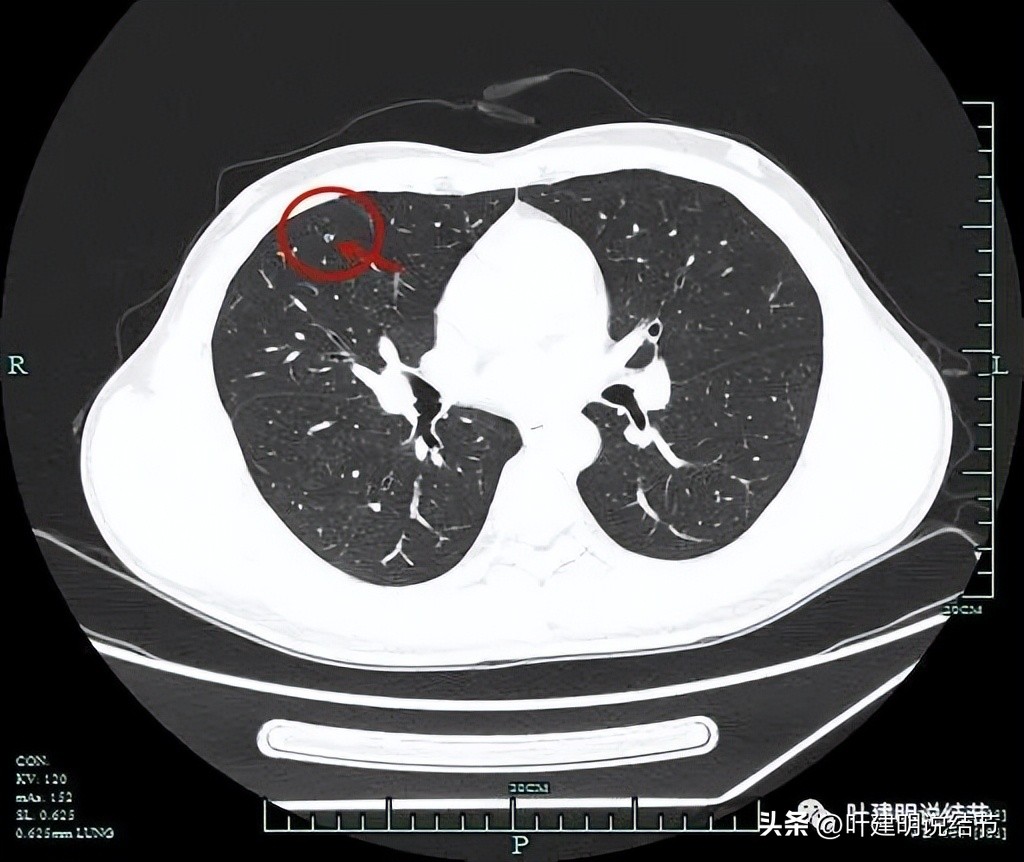

薄层平扫见三处病灶:

病灶2:右中叶靠近肺门部,外侧段支气管壁紧邻处磨玻璃结节,感觉轮廓也较清,边缘不太光滑,考虑恶性范畴的可能性大些。